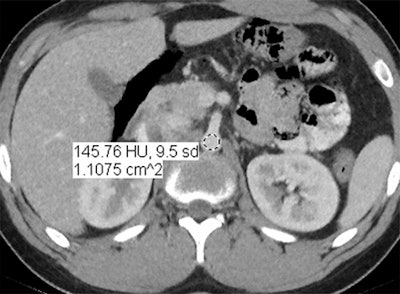

In an objective evaluation, reduced-dose MBIR images had decreased image noise compared with standard-dose 30% ASIR images (for example, 12.7 HU versus 19.4 HU in the aorta, respectively, and 8.7 HU versus 14.2 HU in the liver).